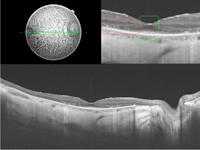

En la imagen superior de la

Figura 1 puede verse una OCT macular realizada con HD- OCT (Cirrus de Zeiss) aumentada, y en la imagen inferior realizada con OCT de última generación DRI-OCT (Atlantis de Topcon).

Figura 1. OCT en voluntarios sanos. Imagen superior: OCT realizada con HD-OCT (Cirrus de Zeiss); imagen inferior: OCT realizada con tecnología DRI-OCT (Atlantis de Topcon). En ambas imágenes pueden distinguirse las cuatro líneas hiperreflectivas de la retina externa (desde la parte vítrea o más interna a la parte coroidea o más externa): membrana limitante externa (MLE), zona de los elipsoides (EZ), zona de interdigitación (IZ) y complejo EPR-membrana de Bruch.